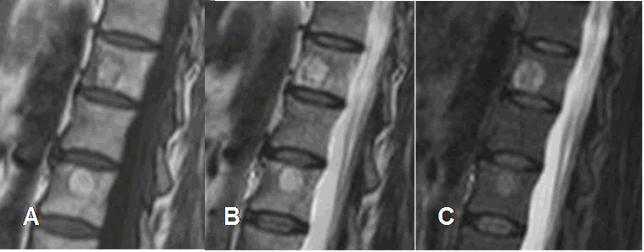

Fig 154. Hemangiomas sintomáticos.

A: RM sagital en T1, B: RM sagital en T2 y C: RM sagital en STIR. Hemangiomas vertebrales hiperintensos en T1 y T2, que no suprimen en STIR, por componente inflamatorio asociado.